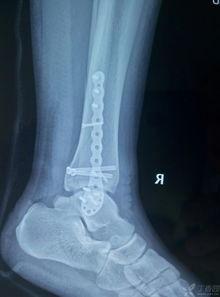

三、脚踝脱臼的图片

为了让你更直观地了解脚踝脱臼,以下是一些真实的图片:

从这些图片中,你可以看到脚踝脱臼后的严重程度,以及肿胀、畸形等症状。